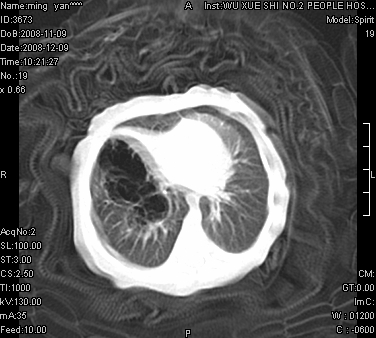

女.30天.咳嗽.喘3天.系三胞胎

考虑右肺下叶先天性肺囊肿,不除外合并右中叶肺发育不全

伴双肺感染

考虑右肺下叶先天性多发性肺囊肿可能。

考虑右肺下叶肺囊肿伴感染,右中叶节段实变或发育不全

这是一个先天性囊性腺瘤样畸形(congenital cystic adenomatid malformation,ccam),属于先天性肺发育异常,最近国外文献重新命名为先天性肺气道畸形(congenital pulmonary airway malformation,cpam),根据发生部位和畸形组织与气管、支气管的关系分成五型。本病以1岁以下婴儿多见,男性多于女性。病因为终末呼吸单元的异常增殖,形成多囊状结构。国内根据影响和病理表现分三型:ⅰ型为单个或多个大囊肿,直径大于2cm;ⅱ型为多个小囊肿,直径小于2cm;ⅲ型为大的非囊肿性病变,但显微镜下观察可见肿块由多发小囊组成(直径小于2mm)。本病可发生于肺内任何一部分,单侧肺占95%,中叶病变相对较少。